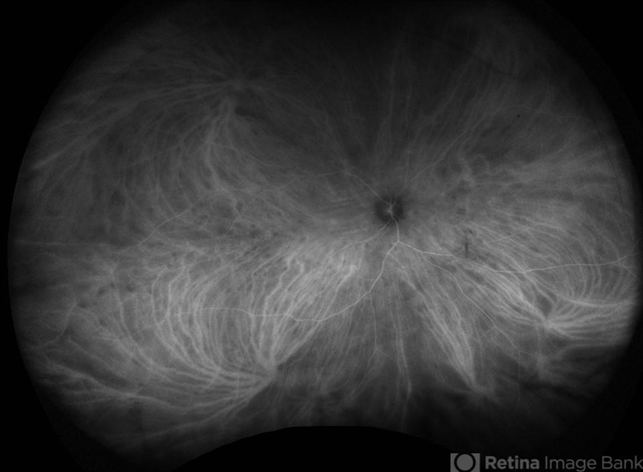

Birdshot Chorioretinopathy - ICG shows numerous scattered small hypocyanescent spots, not necessarily corresponding to lesions seen on FA or clinical examination This image was originally published in the Retina Image Bank® website. Armando L. Oliver, MD. Photographer Moises Castro. Birdshot ICG OD. Retina Image Bank. 2016; 26373. © The American Society of Retina Specialists.